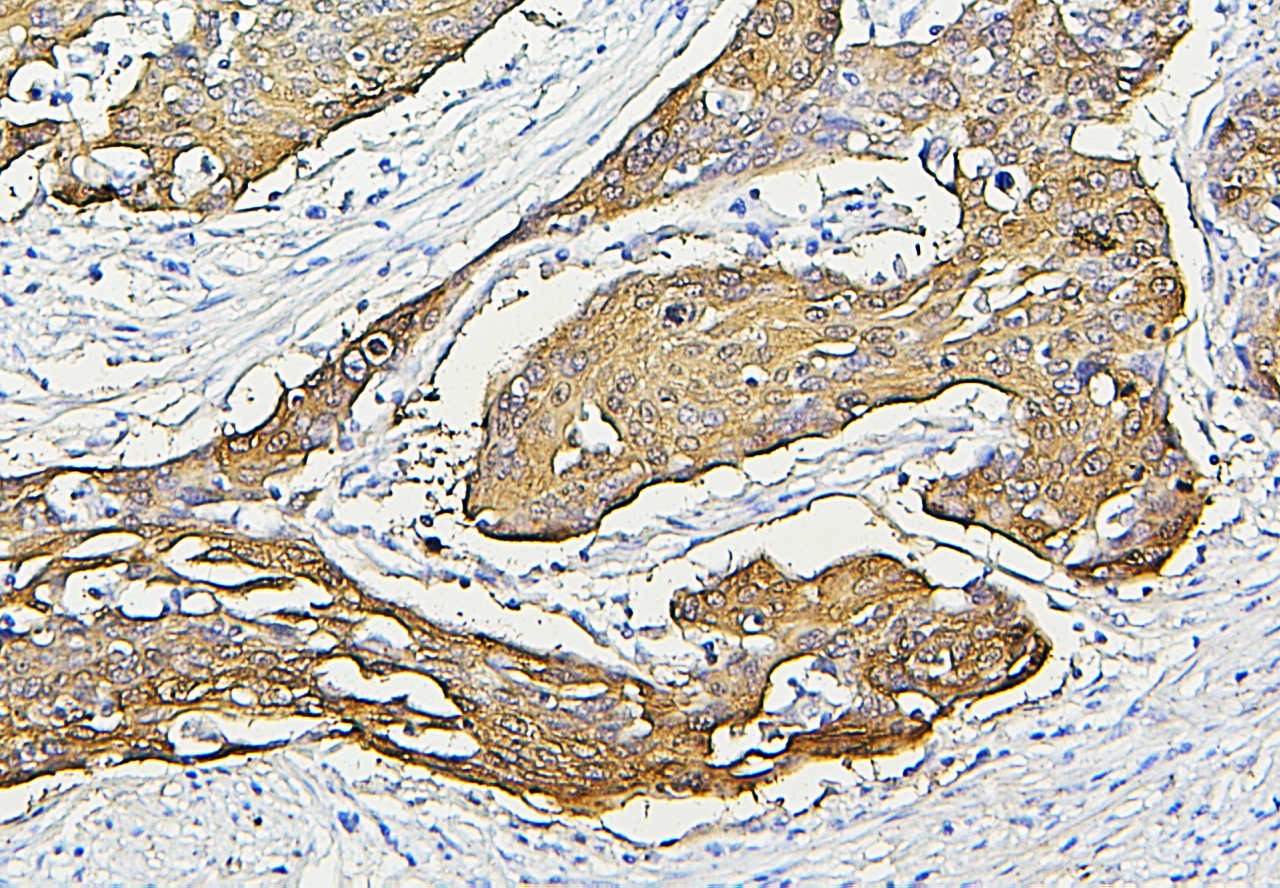

IHC analysis of HSP27/HSPB1 using anti-HSP27/HSPB1 antibody (M00676-5).

HSP27/HSPB1 was detected in a paraffin-embedded section of human oesophagus squama cancer tissue. Biotinylated goat anti-mouse IgG was used as secondary antibody. The tissue section was incubated with mouse anti-HSP27/HSPB1 Antibody (M00676-5) at a dilution of 1:200 and developed using Strepavidin-Biotin-Complex (SABC) (Catalog # SA1021) with DAB (Catalog # AR1027) as the chromogen.